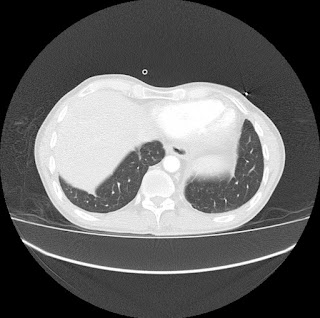

Escanografía